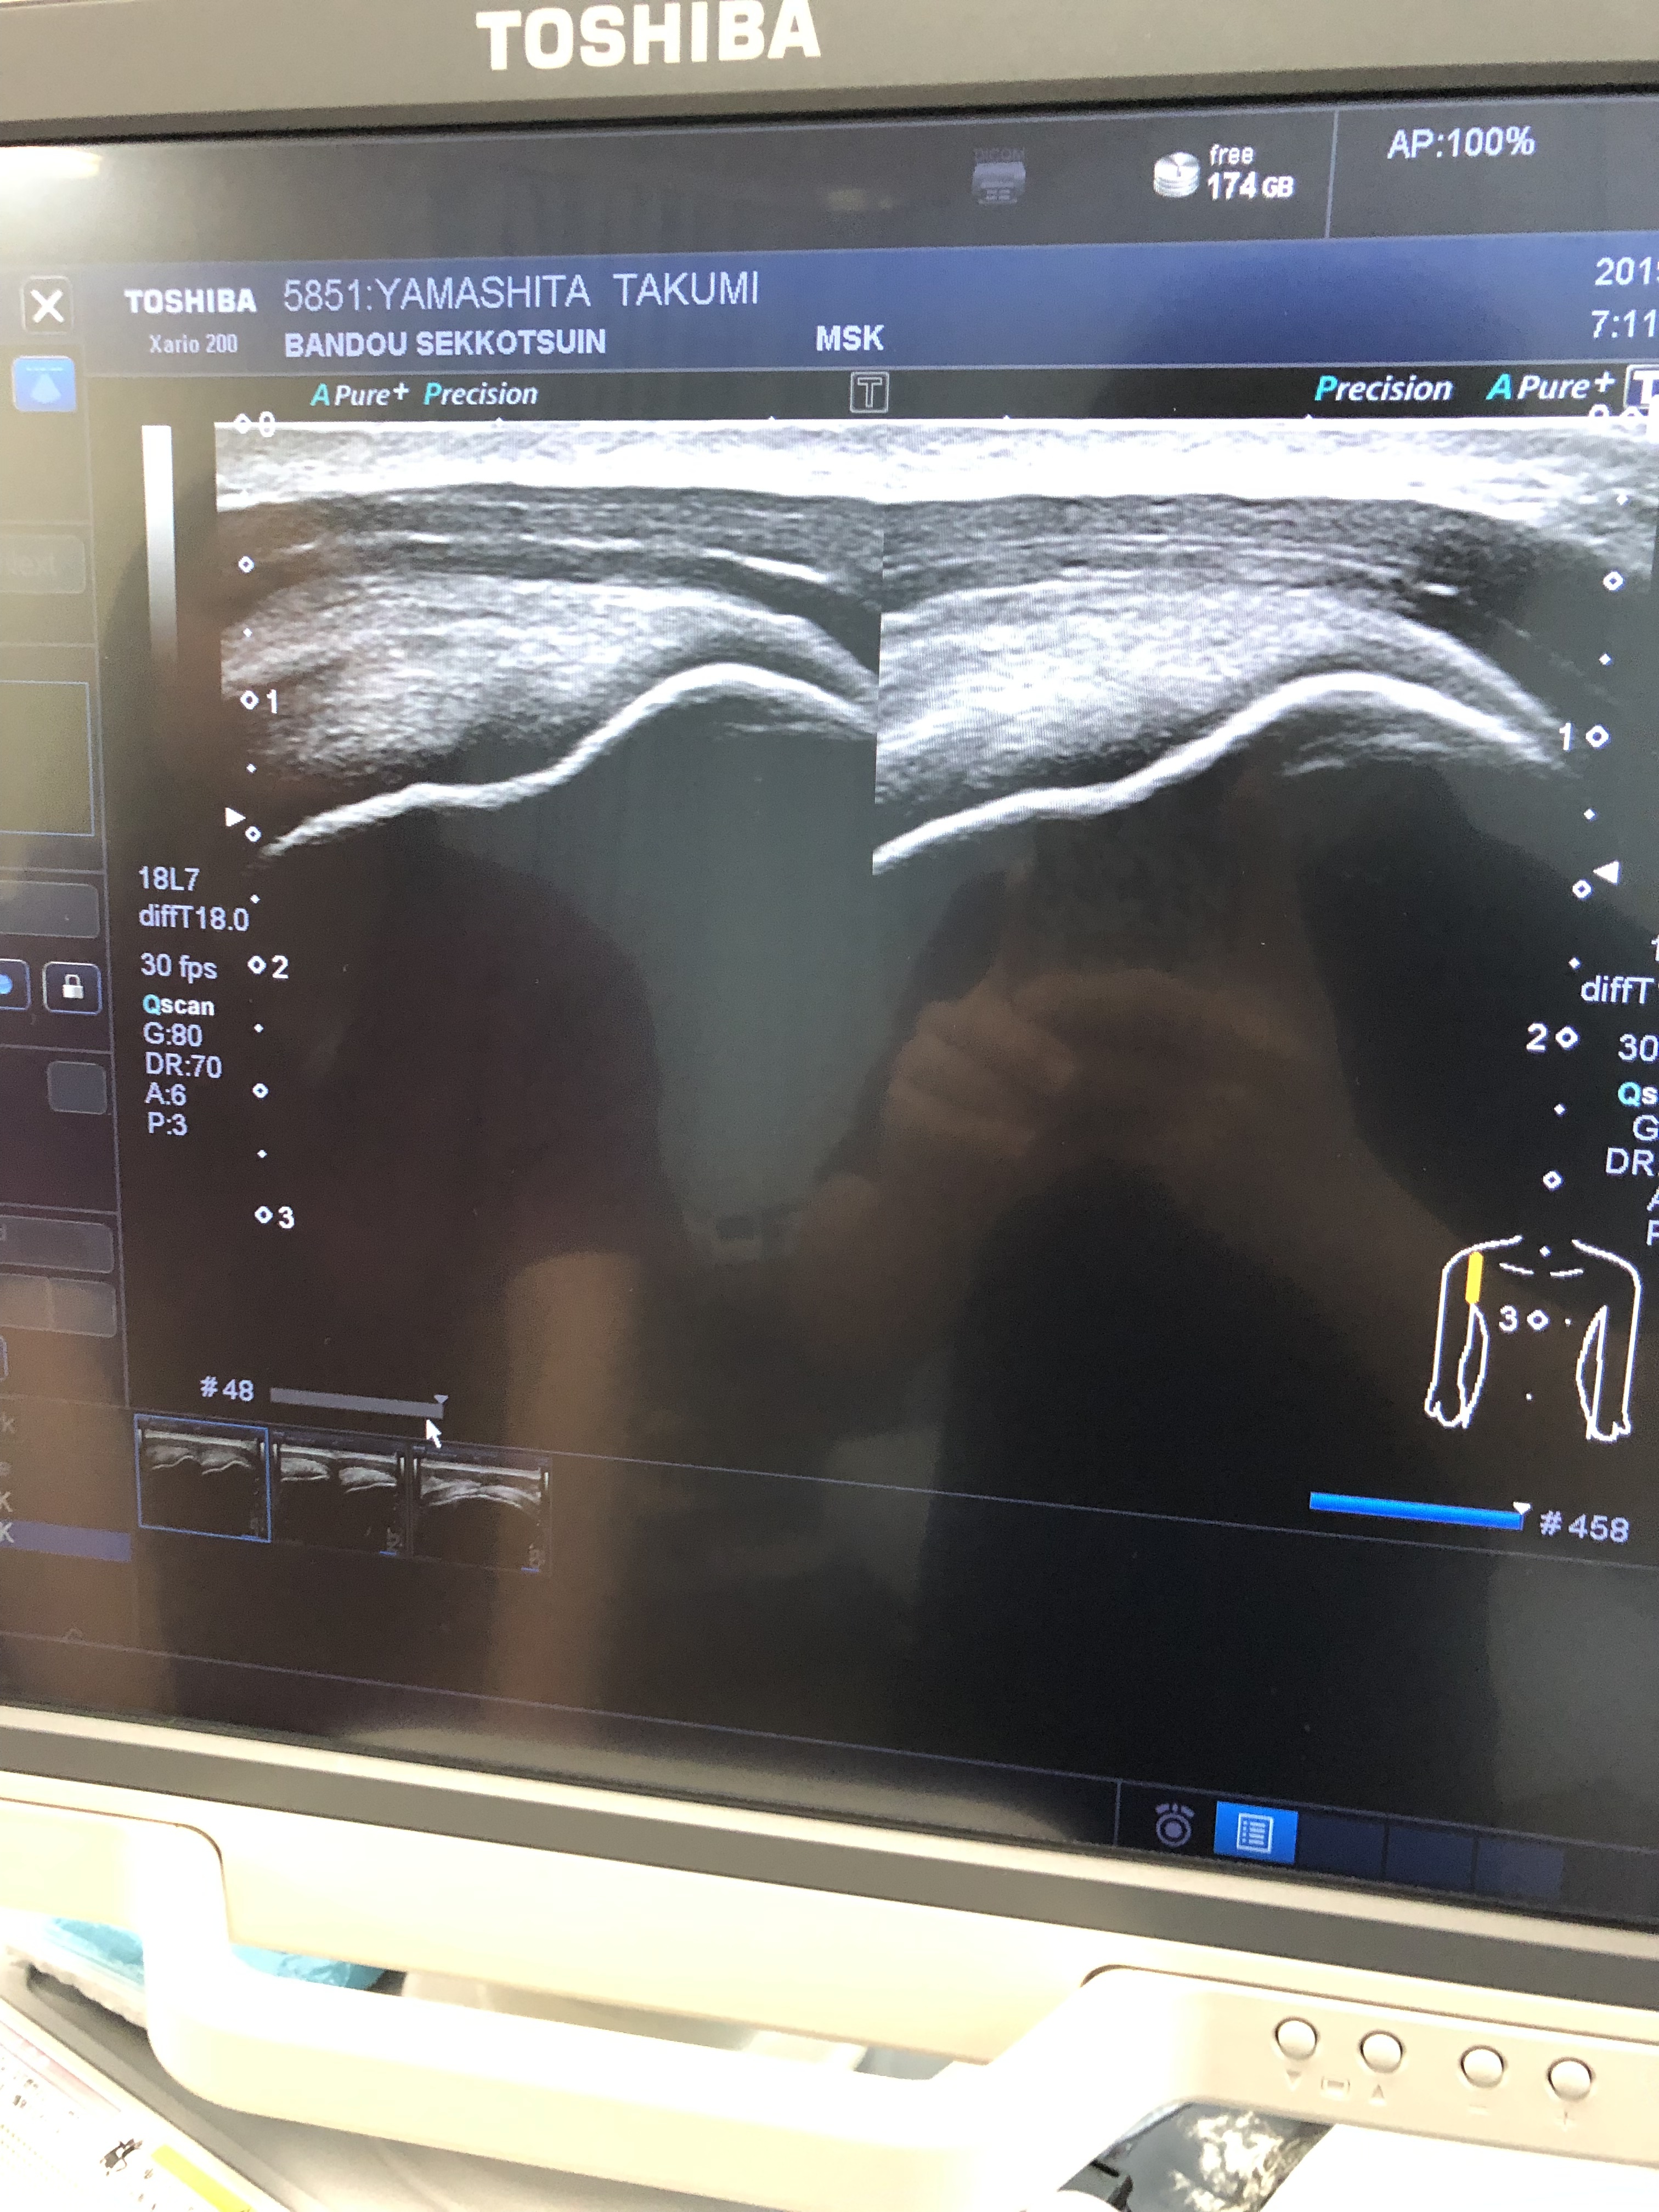

今回はアキュースコープやイオノソンエビデント以外の、超音波エコーについても詳しくお話を聞くことができました。

肩の棘上筋の当て方を練習させていただきました。

下の画像は足の親指の損傷です。

超音波エコーがあると治療の方針や、患者さんへの説明もより明確になるのでいずれ導入したい。。